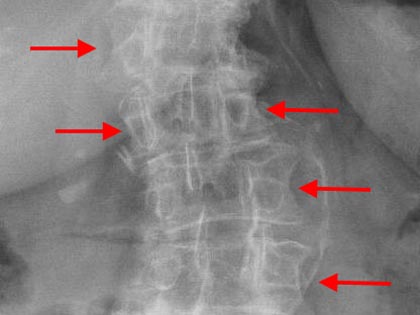

Schmerzsyndrome der Wirbelsäule; Bandscheibenvorfall; Verschleiß der Bandscheiben; Spinalkanalstenose (Verengung des Wirbelkanals); Instabilitäten; Spondylolisthesis (Wirbelgleiten), Myelopathie (Schädigung des Rückenmarkes); Querschnittslähmung; Erkrankungen bei Kinder und Heranwachsenden (z. B. Formveränderungen, Skoliosen, Kyphosen, angeborene Wachstumsstörungen, Verletzungen, Entzündungen, Tumore und Metastasen); Verletzungen des Rückenmarks; Wirbelkörperbrüche; Deformitäten (Formveränderungen, Skoliose, Kyphose); Tumore und Metastasen; Infektionen; Spondylodiszitis (Infektion von Bandscheiben und Wirbelkörper); rheumatische Instabilitäten der Halswirbelsäule sowie zwischen Kopf und Halswirbelsäule; rheumatische Veränderungen der Brust- und Lendenwirbelsäule (z. B. Morbus Bechterew);Verengungen des Foramen magnum; muskulärer Schiefhals; Syndrome durch die erste Rippe; Deformitäten des Thorax (z. B. Trichterbrust, Kielbrust); Erkrankungen und Verletzungen der Rippen; etc.